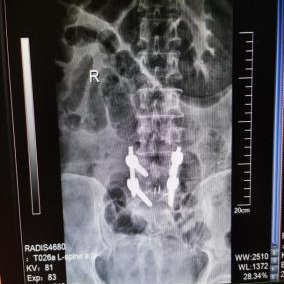

多年来,贵州航天医院各科室紧跟医学前沿,不断强技术、补短板,大力开展新技术、新项目,完成了许多高精尖、高难度、本地区“首例”的技术,填补了医院医疗技术空白,满足了群众日益增长的医疗需求。 贵州航天医院骨科率先在遵义地区开展骨搬移技术,截至目前,已治愈慢性骨髓炎、感染性骨不连、骨缺损、脉管炎、糖尿病足患者200余例,糖尿病足治疗保肢率达到98%。 本期,我们将为大家带来骨科特色技术——骨搬移技术(Ilizarov)。 案例分享 一名59岁的患者,身患糖尿病12年,在来我院3个月前出现了右脚溃烂的症状,来院就诊时,患者的右脚十分红肿,右脚脚趾坏死,伤口处不断流出黑红色脓液,情况十分严重。在接诊到患者时,骨科专家团队高度重视,立刻为患者完善了CT血管造影(CTA)等相关检查,诊断为:2型糖尿病,糖尿病周围血管病变,右糖尿病足。 术 前 考虑到患者情况比较严重,为最大限度保证患者肢体完整,科室专家团队进行了严格的讨论评估,为患者制定了骨搬移技术治疗方案,在征得患者及其家属的同意后,成功通过搬移骨块为患者进行治疗,促进患者病变肢体血管再生。 胫骨横向骨搬移外架固定 清除感染病灶 术后调节外架,通过搬移骨块 促进患肢血管再生 患者在术后三周前来换药,观察到感染得到进一步控制;术后六周复查,患者病变处已愈合,进行CT血管造影(CTA)后可明显观察到足部血管再生。 术后3周 术后6周愈合 CT血管造影见足部血管再生 糖尿病患者全身与局部的问题互为影响,形成恶性循环,糖尿病足溃疡创面迁延不愈,常见干性坏疽、湿性坏疽、趾坏死、深且大的溃疡以及骨髓炎等症状,还可导致脓毒血症,以往为保全生命,患者被迫选择一次或多次截肢。骨搬移技术的发展进步,能在血糖有效控制、局部有效清创下,有效促进患肢微血管再生,改善患肢血供,达到糖尿病足更快治疗康复的目的,并能根据病变情况最大限度的保障患者肢体完整。 什么是骨搬移技术 骨搬移技术是通过使用专用的骨外固定器固定骨段,每天缓慢牵拉,在牵拉搬移过程中,骨段尾部形成新骨及新的软组织,从而修复骨骼缺损及软组织缺损。是治疗大段骨缺损、骨不连、骨感染、肢体畸形的金标准方法,也用于治疗脉管炎、糖尿病足等肢体缺血性疾病。 骨感染缺损 切除感染段 搬移骨段 新骨形成 骨感染根治愈合 骨搬移技术原理 生物组织在持续、稳定、缓慢牵拉下,能刺激细胞分裂、组织再生,骨外固定技术运用该原理,通过持续缓慢调节外固定器形成牵拉张力,促进牵引成骨与相邻组织再生,如神经、血管、肌肉、皮肤等再生,达到治疗大段骨缺损、肢体缺血如糖尿病足等疾病的目的。 骨搬移技术优势 (一)除治疗骨缺损、骨不连外,有更广的适用范围,利用组织再生、血管再生等特性,能大量运用于肢体畸形的矫形、糖尿病足等的治疗。 (二)治疗效果确切,重建肢体外型和功能,极大降低截肢率和残疾率。 (三)明显提高了患者生活质量,极大减轻其家庭及社会负担。 肢体畸形的矫形 慢性骨髓炎 骨段切除 术后1年 濒临截肢的脉管炎术后6周 难愈创面术后3周 贵州航天医院骨科 专家团队 赵学平 骨科主任 主任医师 临床擅长:从事骨科临床工作30余年,对骨科常见疾病的诊治具有丰富的临床经验。 世界中医药联合会脊柱康复专业委员会常务理事,中华中医药学会整脊分会常务委员,中国中西医结合学会骨伤科分会肢体矫形功能重建与康复专家委员会常务委员,中国研究性医院学会骨科创新与转换专业委员会关节外科学组保髋工作委员会常委,中国康复技术转化及发展促进会骨外科与康复技术转化专业委员会常务委员,泛珠三角区域运动医学联盟(PPRD-SMA)理事会常务理事,中国研究型医院学会运动医学专业委员会委员,贵州省中医药学会整脊分会副主任委员,贵州省中西医结合学会银质针专业委员会副主任委员,贵州省康复医学会骨与关节专业委员会常务委员,贵州省人民医院骨科专科联盟常务理事,贵州省康复医学会骨内科专业委员会常务委员,中华医学会贵州省骨科学会委员,贵州省康复医学会脊柱脊髓专业委员会常务委员,贵州省运动医学分会委员,贵州省康复医学会骨与软组织肿瘤专业委员会委员,遵义市医学会创伤分会副主任委员,贵州省康复医学会骨内科专业委员会遵义地区分会常务委员,遵义市医疗事故鉴定、伤残鉴定、工伤鉴定、司法鉴定专家。 长期从事骨科临床研究及教学工作,在国家级、省部级杂志发表论文20余篇,SCI论文2篇,参与主编骨科专著2部,主持省部级科研项目2项,参与指导省部级、市级科研项目6项。 陈明勇 骨科副主任 副主任医师 临床擅长:从事创伤骨科工作约20年,对骨缺损、骨不连、骨肿瘤、肢体畸形等的肢体矫形重建及功能重建,慢性化脓性骨髓炎的根治治疗、糖尿病足的保肢治疗、快速康复理念(ERAS)下的老年骨折的诊治,四肢复杂骨折的诊治,四肢骨折等微创手术治疗具有丰富的临床经验。 2004年毕业于遵义医学院临床专业,曾在中国人民解放军总医院、广西医科大学第一附属医院、上海第六人民医院骨科进修。中国中西医结合学会骨伤科专业委员会横向骨搬移治疗糖尿病足及微血管网再生学组首届委员,遵义市医学会创伤分会常务委员。 瞿 辉 骨科 副主任医师 临床擅长:对骨科的常见病、关节外科、脊柱外科及运动医学疾病的诊治具有丰富的临床经验,熟练掌握骨科手术操作技术。 毕业于遵义医学院临床医学系,2005年前往广州中山大学第一附院骨显微医学部进修学习,2011年前往成都华西医院进修学习,并多次在省内外学习骨科相关知识,是中华医学会骨科分会会员。 赵兴东 骨科 主任医师 临床擅长:擅长骨科的常见病及各种创伤、四肢骨折创伤修复、骨感染、手足疾病的诊治和手足体表畸形的矫形整复,熟练掌握骨科四肢骨病及创伤的手术操作技术,尤其在四肢关节复杂性损伤、手足外伤、组织缺损创面、难治创面的皮瓣修复方面及平足、高弓足矫形方面及四肢慢性疼痛诊治、康复方面具有丰富的临床经验。 硕士研究生,毕业于遵义医学院临床外科系,2015年前往山东省立医院手足外科进修学习;遵义市医学分会创伤分会第一、二届委员,遵义市手外科医学会第二委届员会常务委员;在省级及省级以上期刊发表文章9篇,参编著作2部,参与主持并完成市级课题1项,参与市级课题2项、省级课题1项。 张俊凯 骨科 副主任医师 临床擅长:从事骨科临床工作28年,对创伤骨折、骨感染、骨缺损、骨不连等外科诊治,四肢骨折的微创手术治疗,四肢复杂骨折(如关节内粉碎性骨折、多发骨折等)的损伤控制及手术治疗等具有丰富的临床经验。 1995年毕业于遵义医学院临床专业,2009年前往复旦大学附属医院骨科进修1年。 卢懿明 骨科 副主任医师 临床擅长:从事骨科工作18年,对创伤骨折、四肢骨折的微创手术治疗、四肢复杂骨折(如关节内粉碎性骨折、多发骨折等)的损伤控制及手术治疗,尤其是髋部骨折的PFNA等微创技术,踝关节骨折、膝关节周围骨折的Mipo微创技术等具有丰富的临床经验,开展了4项新技术,发明6项新型专利技术。 2005年毕业于遵义医学院临床专业,2017年,前往南方医科大学第三附属医院骨科进修半年,回院后运用Mipo技术对骨干骨折及干骺端骨折的治疗技术,同时积极开展骨盆骨折、髋臼骨折腹直肌外侧切口的应用;发表了多篇专业论文,经常参与省内外学术交流会授课,获得医院荣誉称号多个。 邬夏荣 骨科 副主任医师 临床擅长:从事骨科工作16年,对四肢复杂骨折、骨肿瘤的诊治,尤其是足踝创伤、慢性踝关节损伤、平足症等诊疗具有丰富的临床经验。 2006年毕业于遵义医科大学临床医学专业,曾在陆军军医大学西南医院进修学习,发表多篇骨科学术论文。 余德怀 骨科 副主任医师 临床擅长:从事骨科工作10余年,对运动医学、骨关节、脊柱外科常见病、多发病的诊治具有丰富的临床经验。 硕士研究生,2011年毕业于遵义医学院临床医学专业,曾前往遵义医科大学附属医院运动医学专业进修学习;是贵州省医学会运动医学分会青年委员,西部关节镜联盟委员;发表多篇骨科学术论文。 冯 乾 骨科 副主任医师 临床擅长:从事骨科工作近20年,熟练掌握骨科多发病及常见病的诊治,尤其对脊柱退变性疾病的诊断及治疗具有丰富的临床经验,主要研究脊柱微创相关治疗方式,能熟练开展椎间孔镜及VBE。 曾前往北京大学第三医院进修学习疼痛及椎间孔镜、首都医科大学友谊医院专业进修脊柱内镜;是贵州省康复医学会第三届脊柱脊髓专业委员会委员;发明专利3项、发表脊柱外科专业论文多篇。 张艳金 骨科 副主任医师 临床擅长:从事骨外科工作16年,对复合伤、多发伤的救治、四肢骨干骨折、关节周围骨折、骨肿瘤、骨髓炎等诊治具有丰富的临床经验。 中共党员,硕士研究生,2006年本科毕业于山西医科大学第二临床医学院,2011年研究生毕业于北京军区总医院;在“老年COPD患者合并髋部骨折的诊治”国际合作课题组研究两年,在老年髋部骨折的诊治方面具有丰富的经验,并发表论文6篇;承担遵义市级课题1项;承担遵义医科大学的临床教学工作,获得遵义医科大学优秀带教老师荣誉。编撰有《骨科疾病诊疗精粹》一书,开展2项新技术,编撰地方规范《务川自治县创伤骨科常见疾病诊疗规范》一书。 赵小锋 骨科 副主任医师 临床擅长:从事骨科临床工作11年,对骨科常见病、多发病诊疗有较为丰富的临床经验,擅长脊柱相关疾病诊断及治疗,尤其是颈、腰、腿疼痛疾病诊断及治疗,擅长胸腰椎骨折微创经皮穿刺内固定术、经皮穿刺椎体成形术、经皮穿刺脊柱内镜下腰椎间盘摘除术、单纯开创腰椎间盘摘除术、腰椎滑脱复位椎间植骨椎融合内固定术、腰椎管狭窄减压融合内固定术及人工髋、膝关节置换术等。 2012年毕业于遵义医学院外科学专业硕士研究生,2019年参加“遵义市115医学人才精英计划”于上海交通大学第一附属医院培训学习,2023年于北京大学第三人民医院脊柱外科进修学习,曾获得遵义市优秀医师荣誉称号。 遵义市手外科第一届委员,遵义市医学会创伤分会第一届委员,遵义市医学会创伤分会第二届委员,贵州省康复医学会第三届脊柱脊髓专业会委员,遵义市医学会烧伤与整形外科学分会委员,发表论文5篇,其中国家级核心期刊1篇,SCI论文1篇,主持市级课题1项并结题,参与市级课题2项。 贵州航天医院骨科简介 基本情况 贵州航天医院(原3417医院)骨科组建于1968年,前身是以创伤和断肢(断指)再植闻名于世的上海市第六人民医院骨科,中国断肢(断指)再植的奠基者、中科院院士陈仲伟等著名专家、学者多次莅临科室指导医疗、教,是贵州省最早拥有专业骨科技术科室之一,在70年代开展了贵州省首例断肢(断指)再植手术。组建50余年来,诊治患者已逾百万,挽救了无数的伤病员,成为了保障遵义地区人民群众健康的重要支撑。 经过几代人的不懈努力,今天的骨科,已由创伤骨科发展至骨病、骨肿瘤、骨结核等领域,现有脊柱外科、关节外科、四肢创伤、手足外科四个亚专科,成为了集医疗、教学、科研于一体的综合学科,是贵州省临床重点专科、遵义市临床重点专科、遵义市骨科临床医学中心、遵义市基层骨科专科联盟理事长单位。 科室目前开放床位110张,共有医护人员50余人,副高级以上专家18人,硕士研究生15人。拥有一流骨科医疗设备多台,每年不定期选派优秀技术骨干到全国各大知名医学院校进修、学习、参观、交流,并邀请国内、国外知名专家教授来院进行交流、指导,通过不断引进国内外先进的诊疗技术,科室医疗技术水平稳步提升,为广大人民群众提供了优质的医疗服务。 专科特色 骨一科 (一)骨缺损、骨不连的肢体与功能重建 胫骨横向骨搬移技术治疗糖尿病足: (二)慢性骨髓炎的根治治疗 (三)肢体缺血性疾病如糖尿病足、脉管炎的保肢治疗 (四)皮瓣修复 (五)复杂创伤的治疗 (六)老年髋部骨折及小儿骨折快速手术 老年髋部骨折: 骨二科 (一)胸腰椎骨折微创经皮椎弓根螺钉固定术 (二)老年性骨质疏松性患者腰椎滑脱脊柱内固定术(骨水泥螺钉) (三)V形双通道脊柱内镜技术(VBE)腰椎融合术治疗腰椎退行性疾病 (四)老年性骨质疏松性骨折(PVP/PKP)术 (五)人工髋关节置换术 (六)双侧股骨头坏死人工全髋关节置换 (七)右侧全髋置换术后假体周围骨折翻修 (八)人工膝关节置换术 (九)人工膝关节假体松动翻修 (十)关节镜技术 传统手术切口 关节镜技术切口 诊疗范围 骨一科 1.四肢创伤、矫形。 2.手、足踝外科。 骨二科